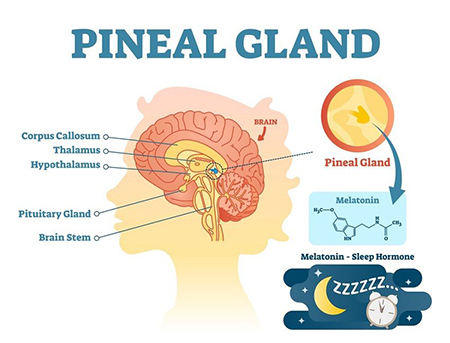

غده صنوبری به شکل مخروط کاج است و به اندازه یک نخود است و قطر آن تقریباً 8 میلی متر است. در اپیتالاموس، ناحیه ای از مغز که بین دو نیمکره قرار دارد و توسط تالاموس احاطه شده است، قرار دارد. غده صنوبری از پینهآلوسیتها تشکیل شده است که سلولهای تخصصی هستند که ملاتونین، هورمونی که چرخه خواب و بیداری را تنظیم میکند، تولید و ترشح میکنند.

تولید ملاتونین توسط بخشی از مغز به نام هسته سوپراکیاسماتیک (SCN) که در هیپوتالاموس قرار دارد، کنترل می شود. SCN اطلاعات مربوط به چرخه های نور و تاریکی را از چشم دریافت می کند و سیگنال هایی را برای تنظیم تولید ملاتونین به غده صنوبری ارسال می کند. در طول روز، زمانی که نور بیشتری وجود دارد، SCN سیگنال هایی را برای سرکوب تولید ملاتونین ارسال می کند. در شب، زمانی که نور کمتری وجود دارد، SCN سیگنال هایی را برای تحریک تولید ملاتونین ارسال می کند که به بهبود خواب کمک می کند.

غده صنوبری علاوه بر نقشی که در تنظیم چرخه خواب و بیداری دارد، در تنظیم خلق و خو و رشد جنسی نیز نقش دارد. مطالعات نشان داده اند که افراد مبتلا به افسردگی و سایر اختلالات خلقی سطوح پایین تری از ملاتونین دارند که نشان می دهد غده صنوبری ممکن است در این شرایط نقش داشته باشد. غده صنوبری همچنین با تولید سطوح بالاتر ملاتونین در دوران کودکی و سطوح پایین تر در دوران نوجوانی به تنظیم شروع بلوغ کمک می کند.

• تنظیم ریتم های شبانه روزی : غده صنوبری نقش کلیدی در تنظیم ریتم های شبانه روزی بدن ایفا می کند که تغییرات فیزیکی، ذهنی و رفتاری است که پس از یک چرخه 24 ساعته انجام می شود. این در درجه اول به دلیل تولید و تنظیم ملاتونین توسط غده صنوبری است که به همگام سازی ساعت داخلی بدن با محیط خارجی کمک می کند.